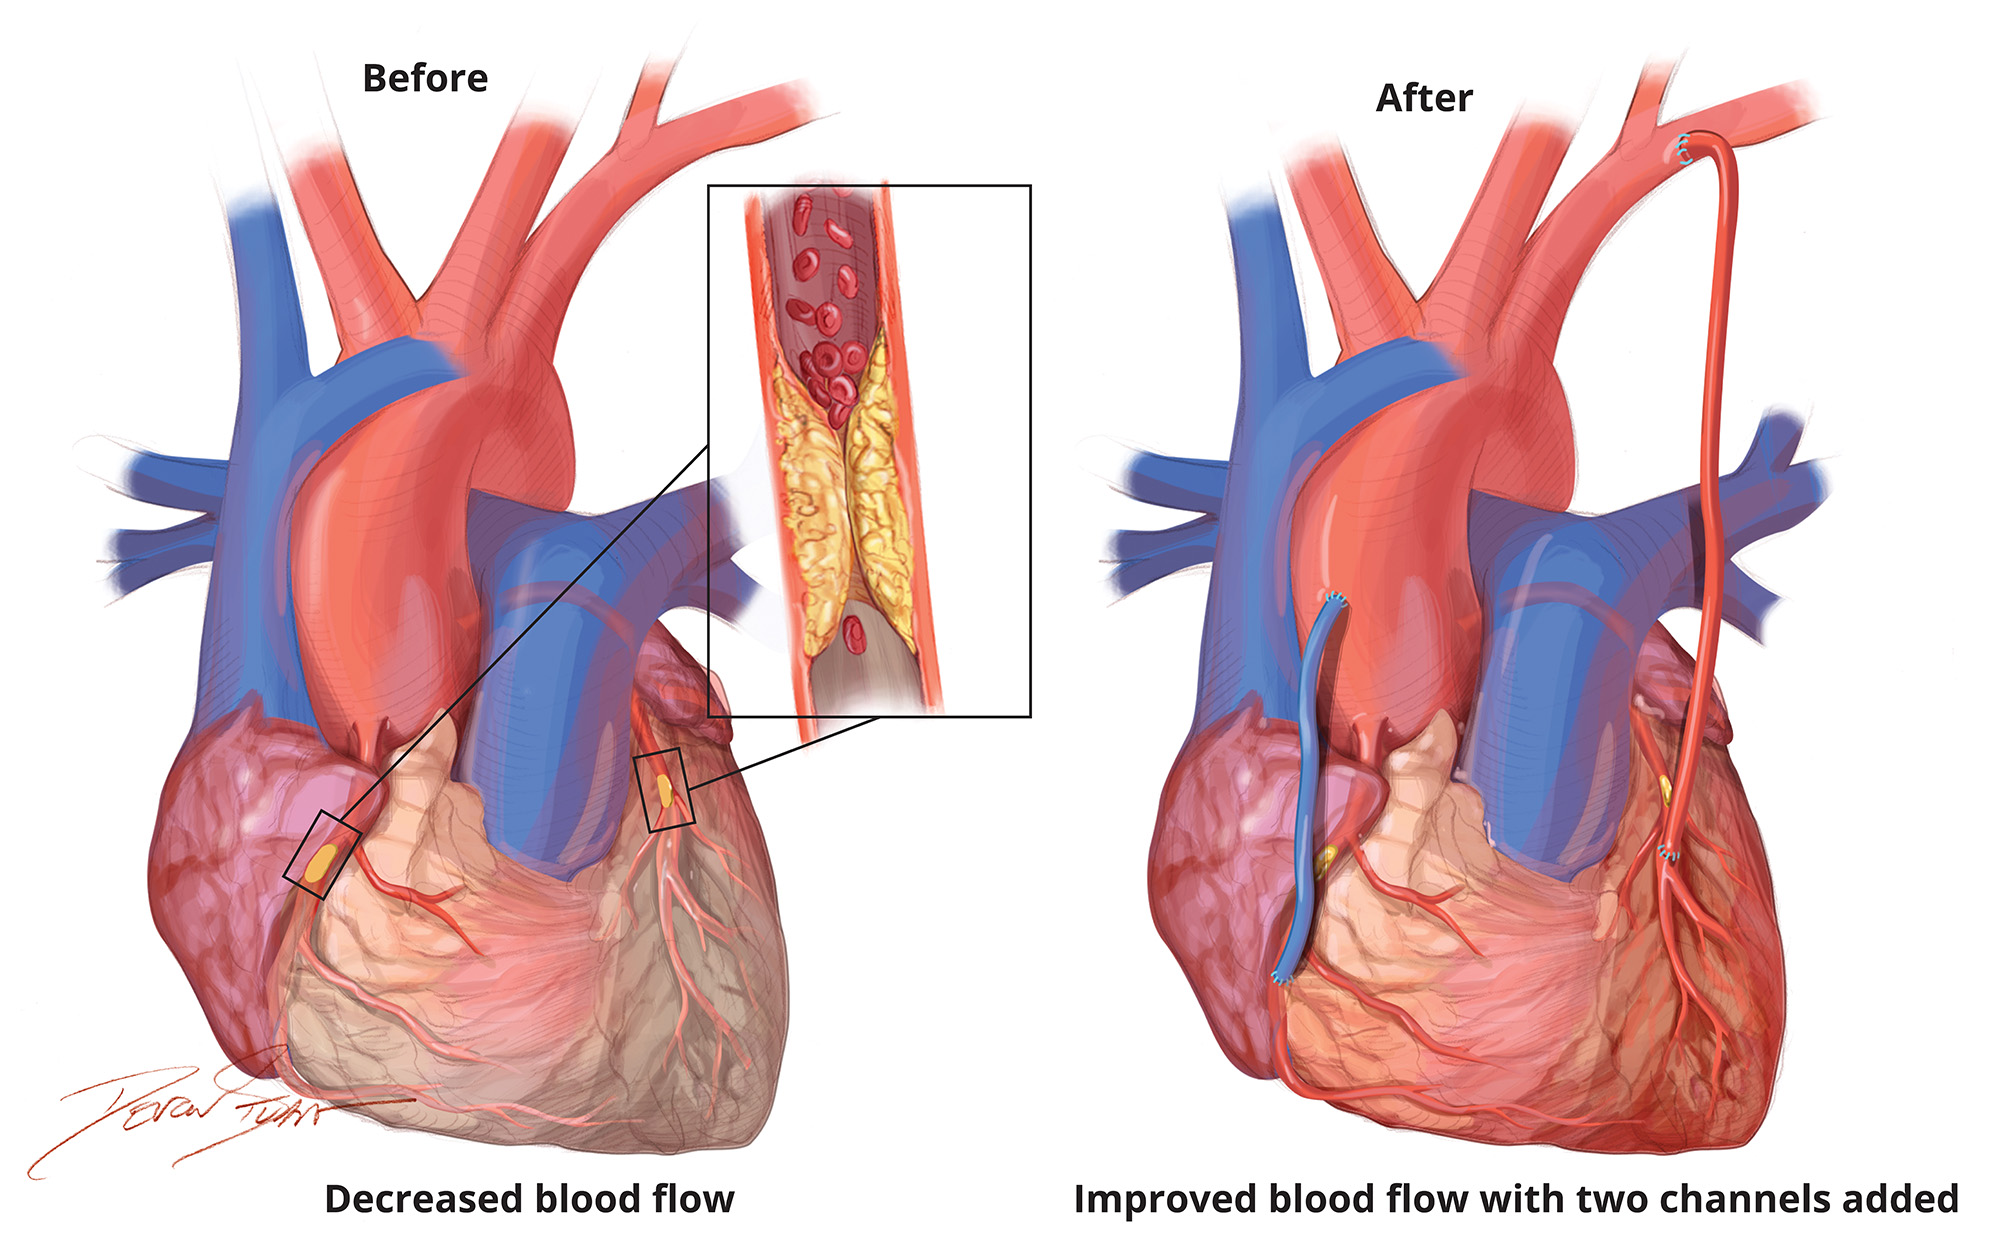

Open Heart Surgery

Perform complex heart surgeries such as coronary artery bypass grafting (CABG), heart valve repair or replacement, and congenital heart defect

Coronary artery bypass graft (CABG)

CABG is one of the most common types of open heart surgery. The coronary arteries supply the heart with blood. If the arteries become blocked or narrowed due to heart disease, a person may be at risk of a heart attack. The operation involves taking a healthy blood vessel from another part of the body and using it to bypass the blocked arteries